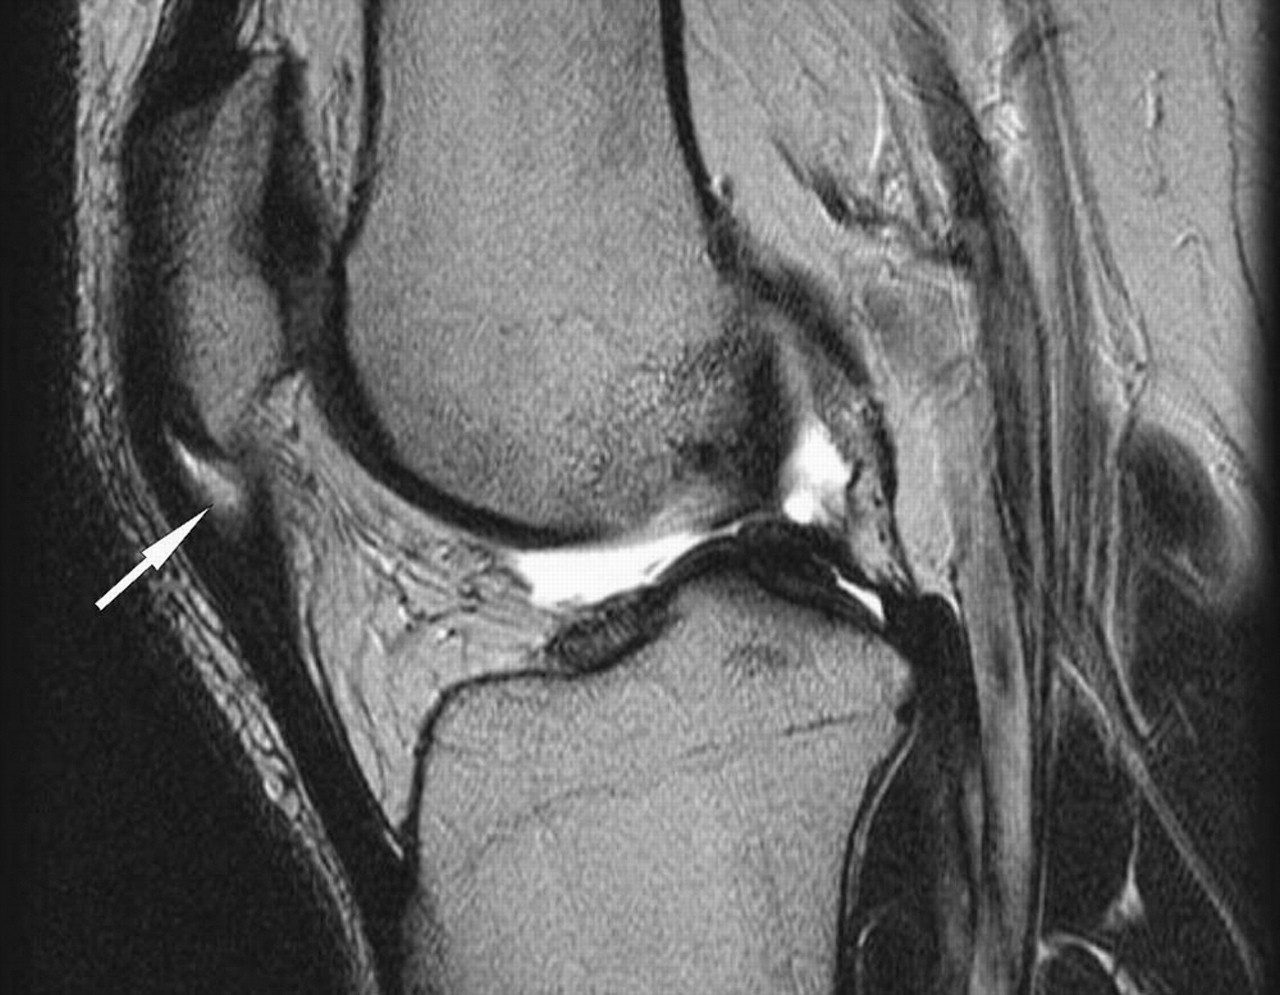

- Podemos complementar la valoración con pruebas de imagen para realizar un diagnóstico diferencial, sin embargo, exámenes como la ecografía no han resultado determinantes en el diagnóstico de la Tendinitis Rotuliana, ya que las alteraciones en la imagen del tendón pueden también estar presentes en sujetos asintomáticos.

- Lesiones osteocondrales (derrames).